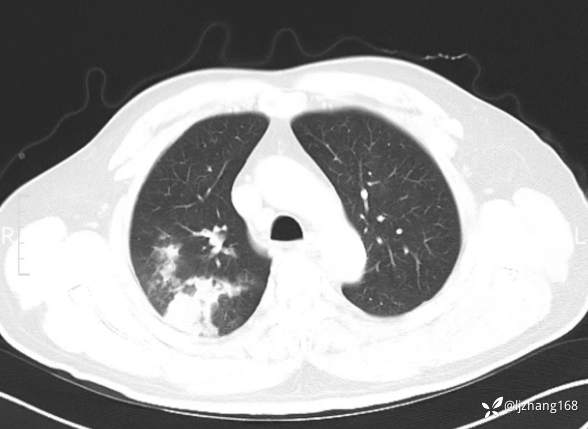

中年男患,右肺团片影,炎症0R肿瘤?

简要病史: 20+天前患者因受凉后出现阵发性咳嗽,咳少量白色粘痰,痰易咳出,伴活动后气短,伴纳差、乏力、全身酸痛,伴多汗,无痰中带血及咯血,无发热、畏寒及寒战,无潮热、盗汗,无夜间阵发性呼吸困难及端坐呼吸,无声嘶,无头晕、头痛,无黑矇、晕厥及意识障碍,无腹痛、呕血及黑便等不适,遂就诊于当地医院予以输液等治疗后未见明显好转(具体诊疗不详),现为进一步诊治就诊于我院门诊,以“右肺占位”收入我科。病来饮食欠佳,近期体重下降(具体不详)。既往糖尿病病史7+年,未规律监测血糖,血糖控制不佳。否认“高血压、冠心病及慢性肾脏病”等慢性疾病史。否认“肝炎、结核、伤寒”等传染病史。否认食物、药物过敏史。否认外伤、输血史,预防接种史不详。

辅助检查:糖化血红蛋白12.3%。肺炎支原体IgG、IgM、呼吸道合胞病毒均未见明显异常。胸部CT:右肺上叶阻塞性肺炎。